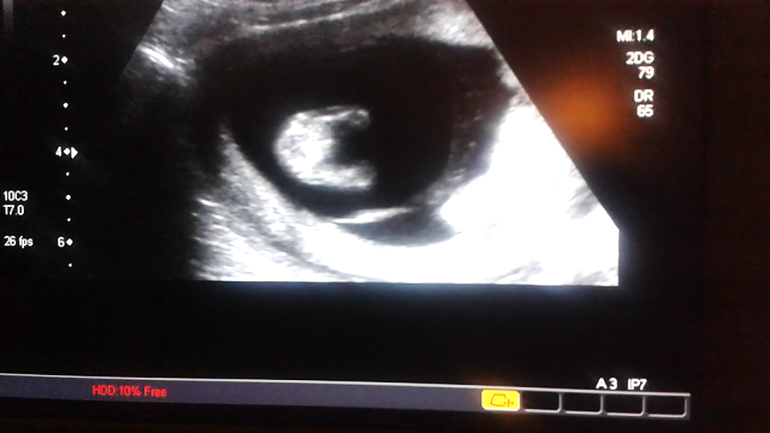

Нужно мнение зала:) пол по узи в 13 недель.

УЗИ, КТГ, доплерУзист сказал.что не видно. Хотя отчетливо мелькает какой-то "шарик". Пытала врача,мальчик ли. Она молчит. Зато подруга уверена.что да😃 а вы как думаете? Разве такое бывает у девочек?

Фото между ножек снизу.